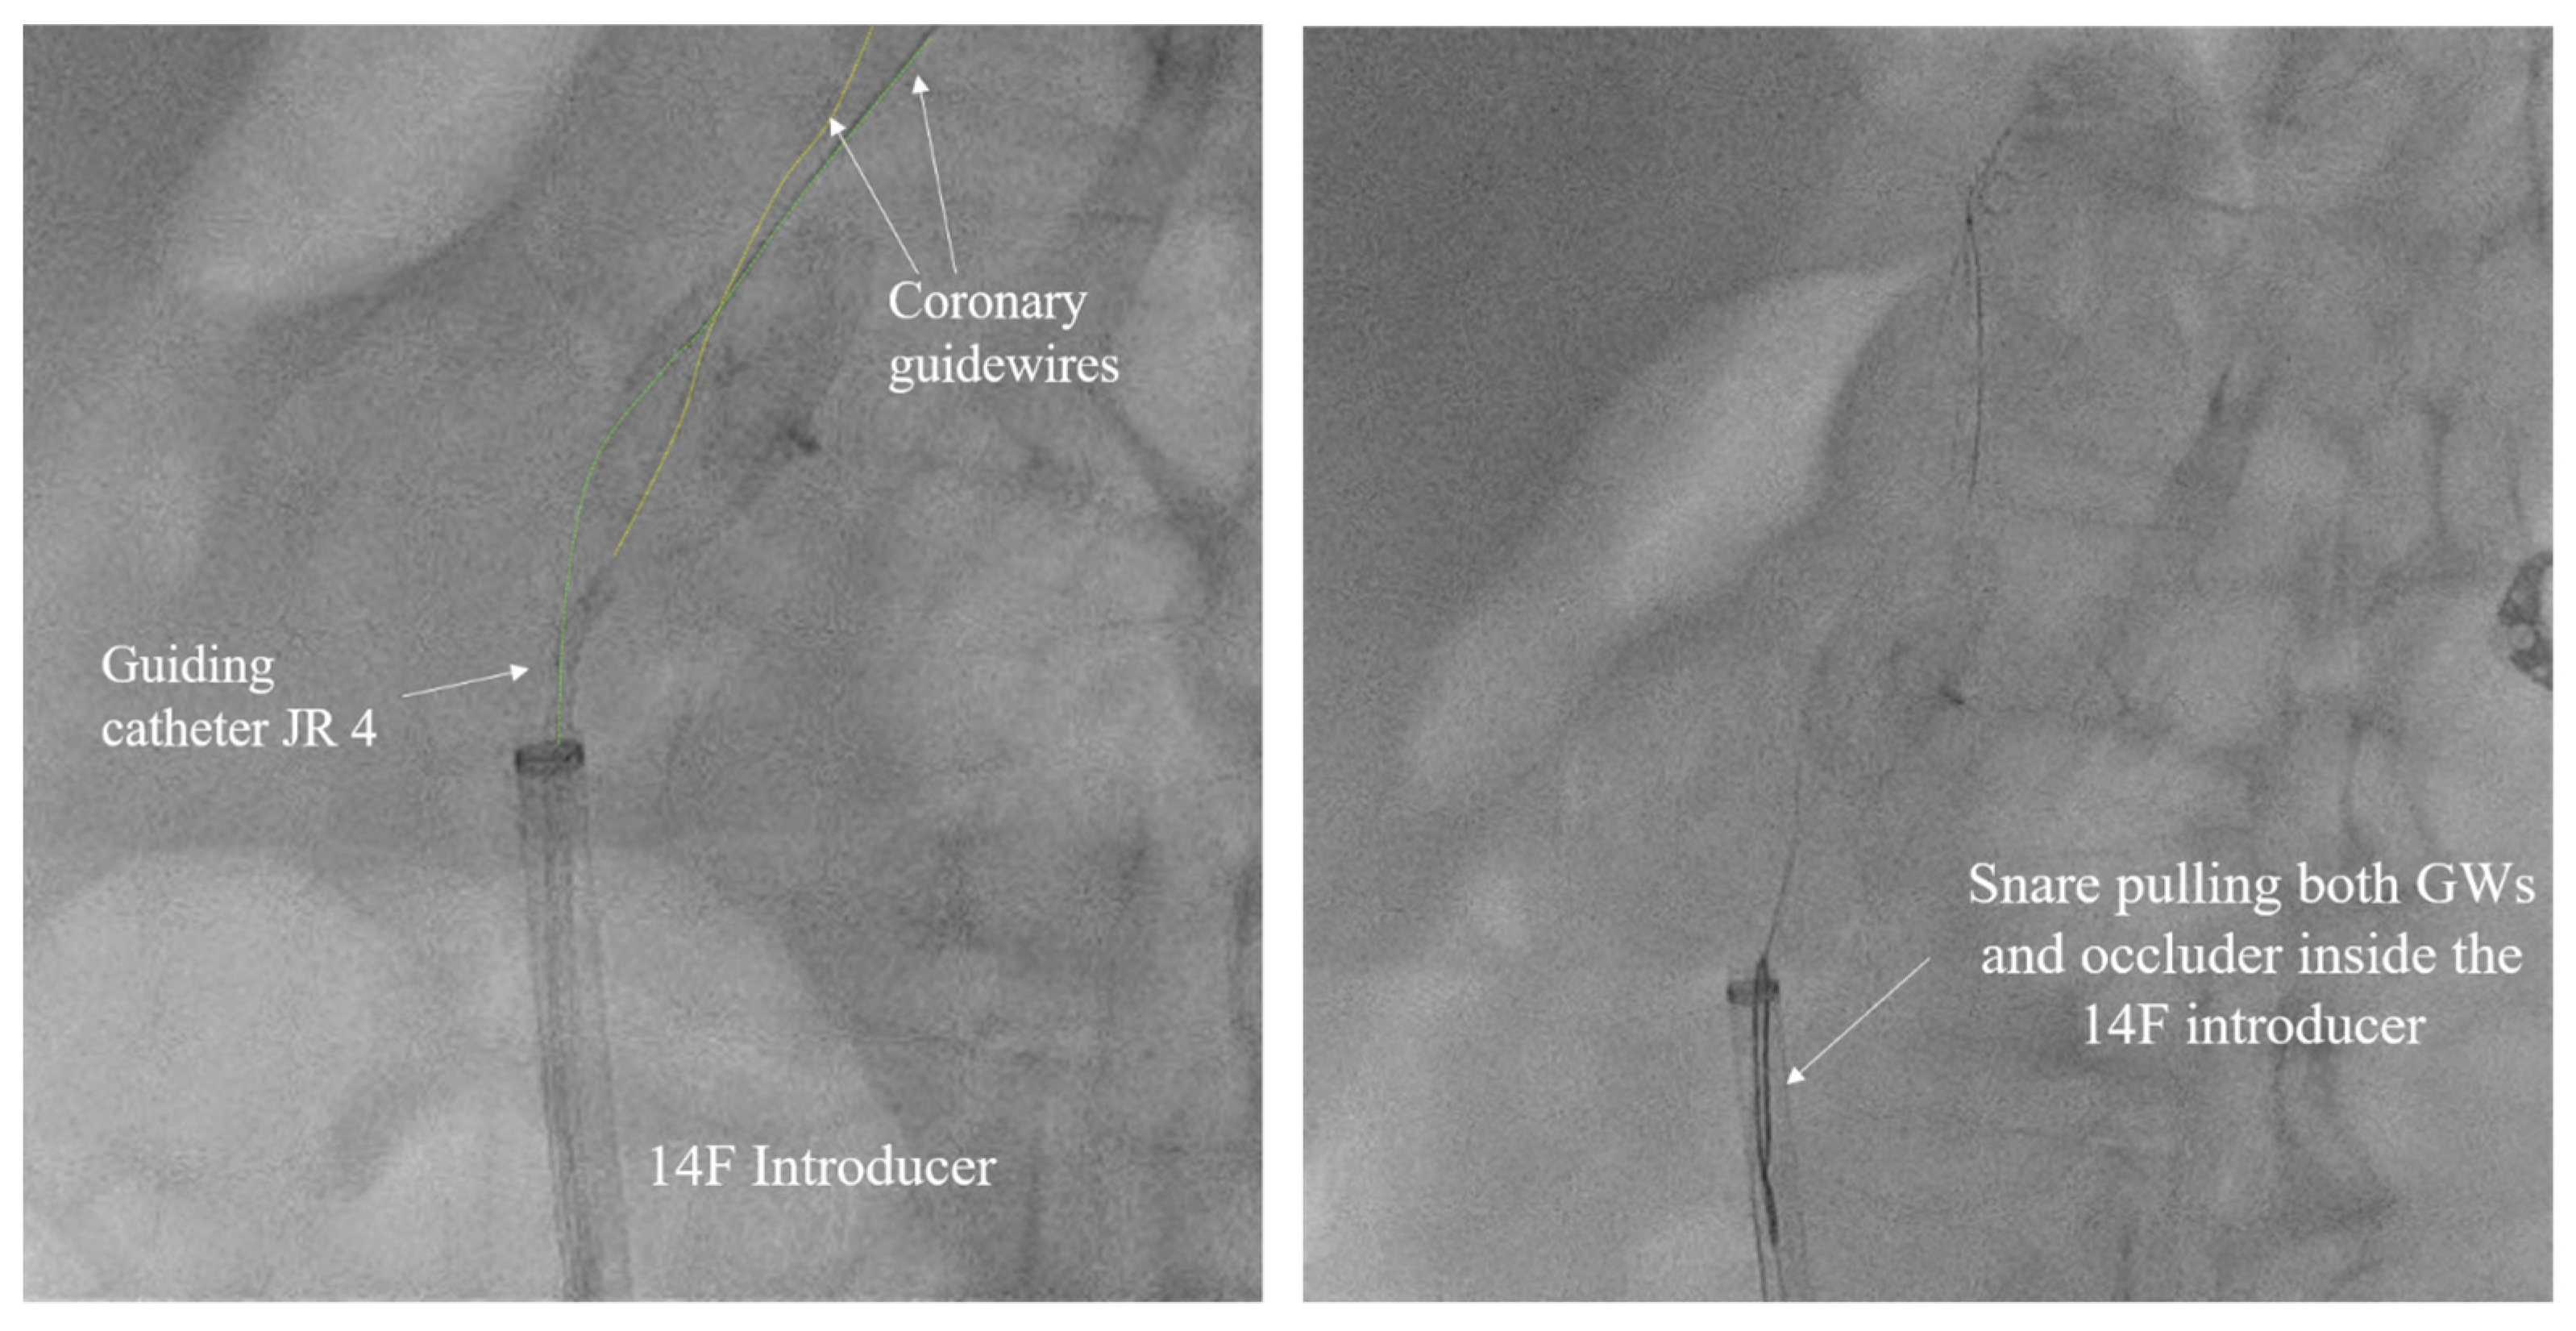

The left common femoral artery (CFA) was promptly punctured, followed by the placement of a 14F introducer. Several attempts were undertaken to recapture the right atrial disc button of the PFO occluder using a 15 mm Amplatz Goose Neck snare (Medtronic, Minneapolis, MN, USA), but these efforts were unsuccessful. The position of the device, trapped within the aorta, with the right atrial disk button opposite to the aortic wall, disabled access to the device even with a 6 F guiding catheter Judkins right (JR) 4 used to navigate and reach the occluder button. This step was succeeded by the introduction of two coronary guidewires with higher tip loads, namely the Pilot 150 (Abbott Vascular, Santa Clara, CA, USA) and Samurai RC (Boston Scientific, Marlborough, MA, USA), one through the JR 4 guiding catheter already positioned and the second one directly through the 14F introducer. These wires were subsequently maneuvered, one by one, through the mesh of the PFO occluder (Figure 5). The JR 4 guiding catheter was withdrawn, and a 15 mm Amplatz Goose Neck snare was introduced through the 14F introducer. Following this, two coronary guidewires were captured proximally to the PFO occluder using a 15 mm Amplatz Goose Neck snare and subsequently pulled, facilitating the partial retraction of the PFO occluder into the 14F introducer (Figure 5, Video S1).

Figure 5.

Amplatz Goose Neck snare complemented with two coronary guidewires (GWs) in a unique system for occluder retrieval.

The entire wire–occluder system within the 14F introducer was then carefully retracted to the common femoral artery to a position deemed suitable for surgical extraction via arteriotomy, which was achieved successfully (Figure 6).